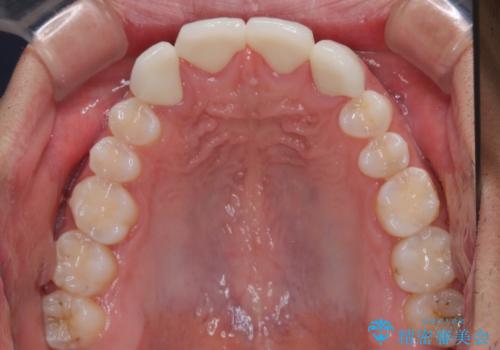

- 歯の欠損による前歯のすきっ歯を気にして来院された患者様です。

矯正治療かオールセラミックか、治療の選択がありましたが、熟考の末オールセラミッククラウンにて補綴することとしました。

ひとつひとつの歯の幅は非常に大きくなりましたが、手っ取り早く隙間が改善されたとのことで、大変満足していらっしゃいました。